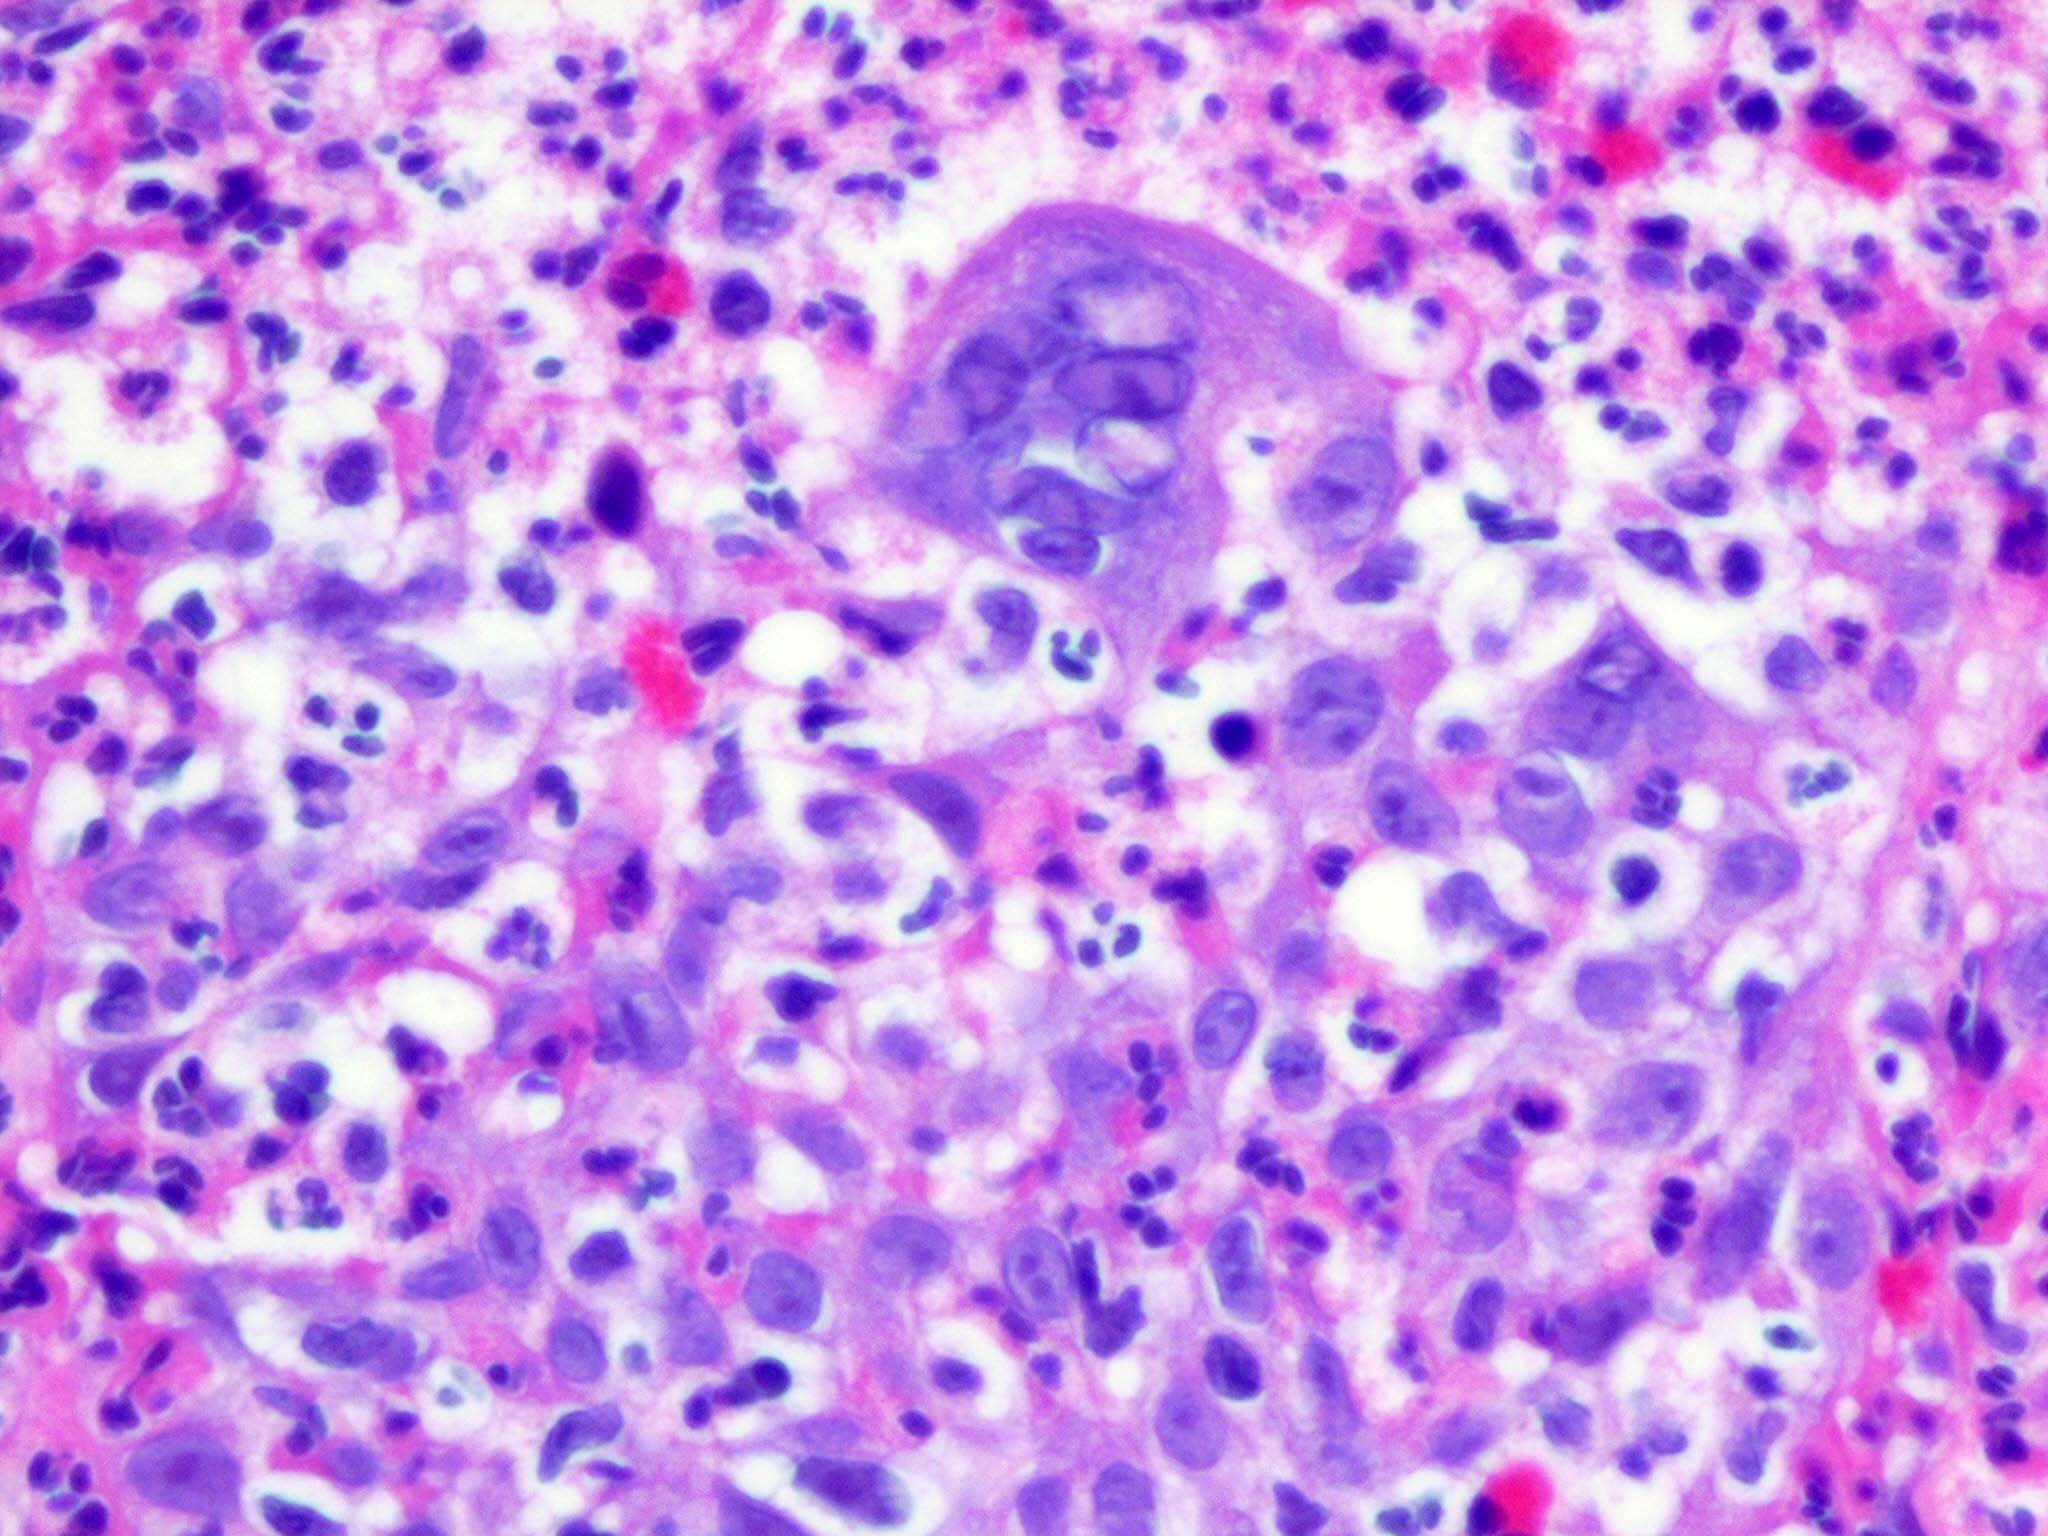

Herpes simplex = العقبول البسيط